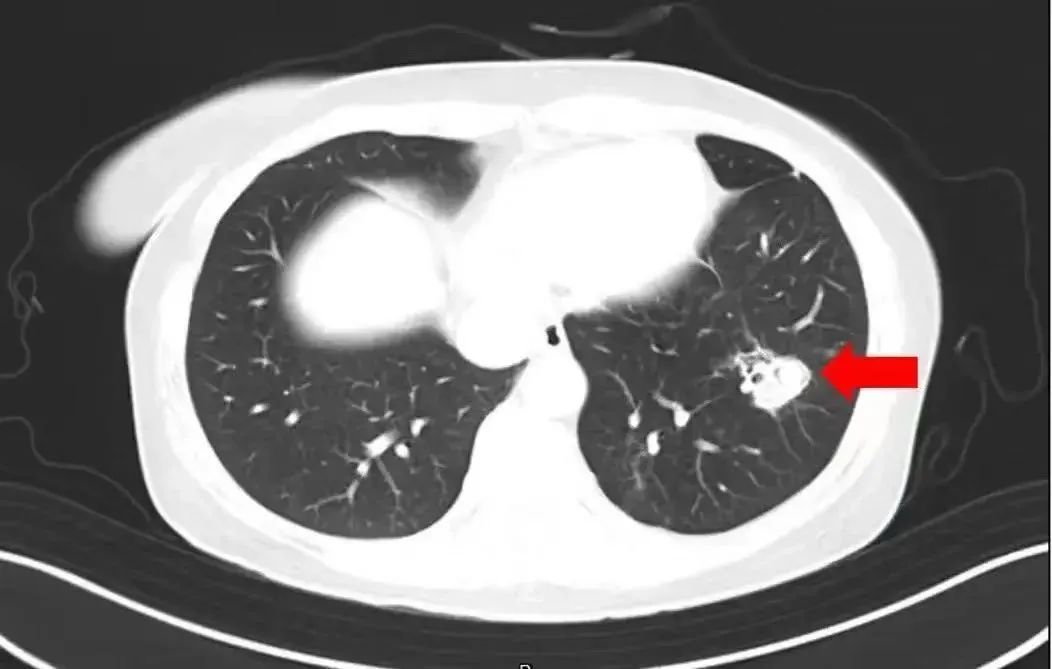

医生通过问诊了解到,沈女士在整理衣柜时发现里面长了霉斑,于是对衣柜做了清理,但清理时没戴口罩 。为进一步确诊病情,医生为沈女士进行纤维支气管镜检查及肺泡灌洗液病原体检测,果然发现气道壁上有大量白色菌斑,化验后确认是曲霉菌。